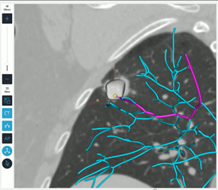

Før bronkoskopiproceduren overføres patientens CT-skanning til LungVisions planlægningssoftware, således at der kan rekonstrueres et virtuelt trakeobronkialt træ, og læsionen kan markeres og ruten planlægges ud fra både axiale, koronale og sagittale planer.

Figur 3: Rekonstrueret luftvejstræ

Under proceduren placeres en røntgenfast plade under undersøgelseslejet (karbonleje), som analyserer placeringen af strukturerne i thorax i forbindelse med gennemlysning og genereringen af real time billeder, og som assisterer bronkoskopiteamet til at indstille fluoroskopet mest optimalt i forhold til infiltratets placering.

Figur 4: Vejledning til justering af C-bue

De softwarebehandlede CT-billeder med ruten og markeringen af læsionen sammenholdes med de real time billeder som dannes forud for proceduren med patienten på lejet. Fluoroskopet roteres omkring patienten, og systemet vil herefter omdanne gennemlysningsbillederne til CT-lignende rekonstruktioner – den såkaldte C-arm based tomography (CABT).

Figur 5: Rekonstruerede CT-lignende optagelser (CABT)

Sammenkoblingen mellem CABT og den præprocedurale CT-skanning softwarebehandles og overføres til af LungVision-systemet, som er koblet op på den konventionelle C-bue. Herefter genereres et overlejrende fluoroskopisk image (augmented fluoroskopi) med angivelse af læsionen såvel som ruten oven på de billeder som det konventionelle fluoroskop danner under proceduren, og som nu i real time guider bronkoskopøren til læsionen. Når skopet med kateteret er placeret ud for læsionen, kan placeringen efterfølgende kontrolleres yderligere med fx radial EBUS. Når tumorslagskyggen er konfirmeret, kan der efterfølgende biopteres fra området under real time vejledning af det forbedrede fluoroskopiske billede, som også er i stand til at vise biopsiværktøjet i læsionen, hvorved den diagnostiske sensitivitet øges.

Figur 6: Augmented fluoroskopi

Figur 7: ”Tool in lesion”